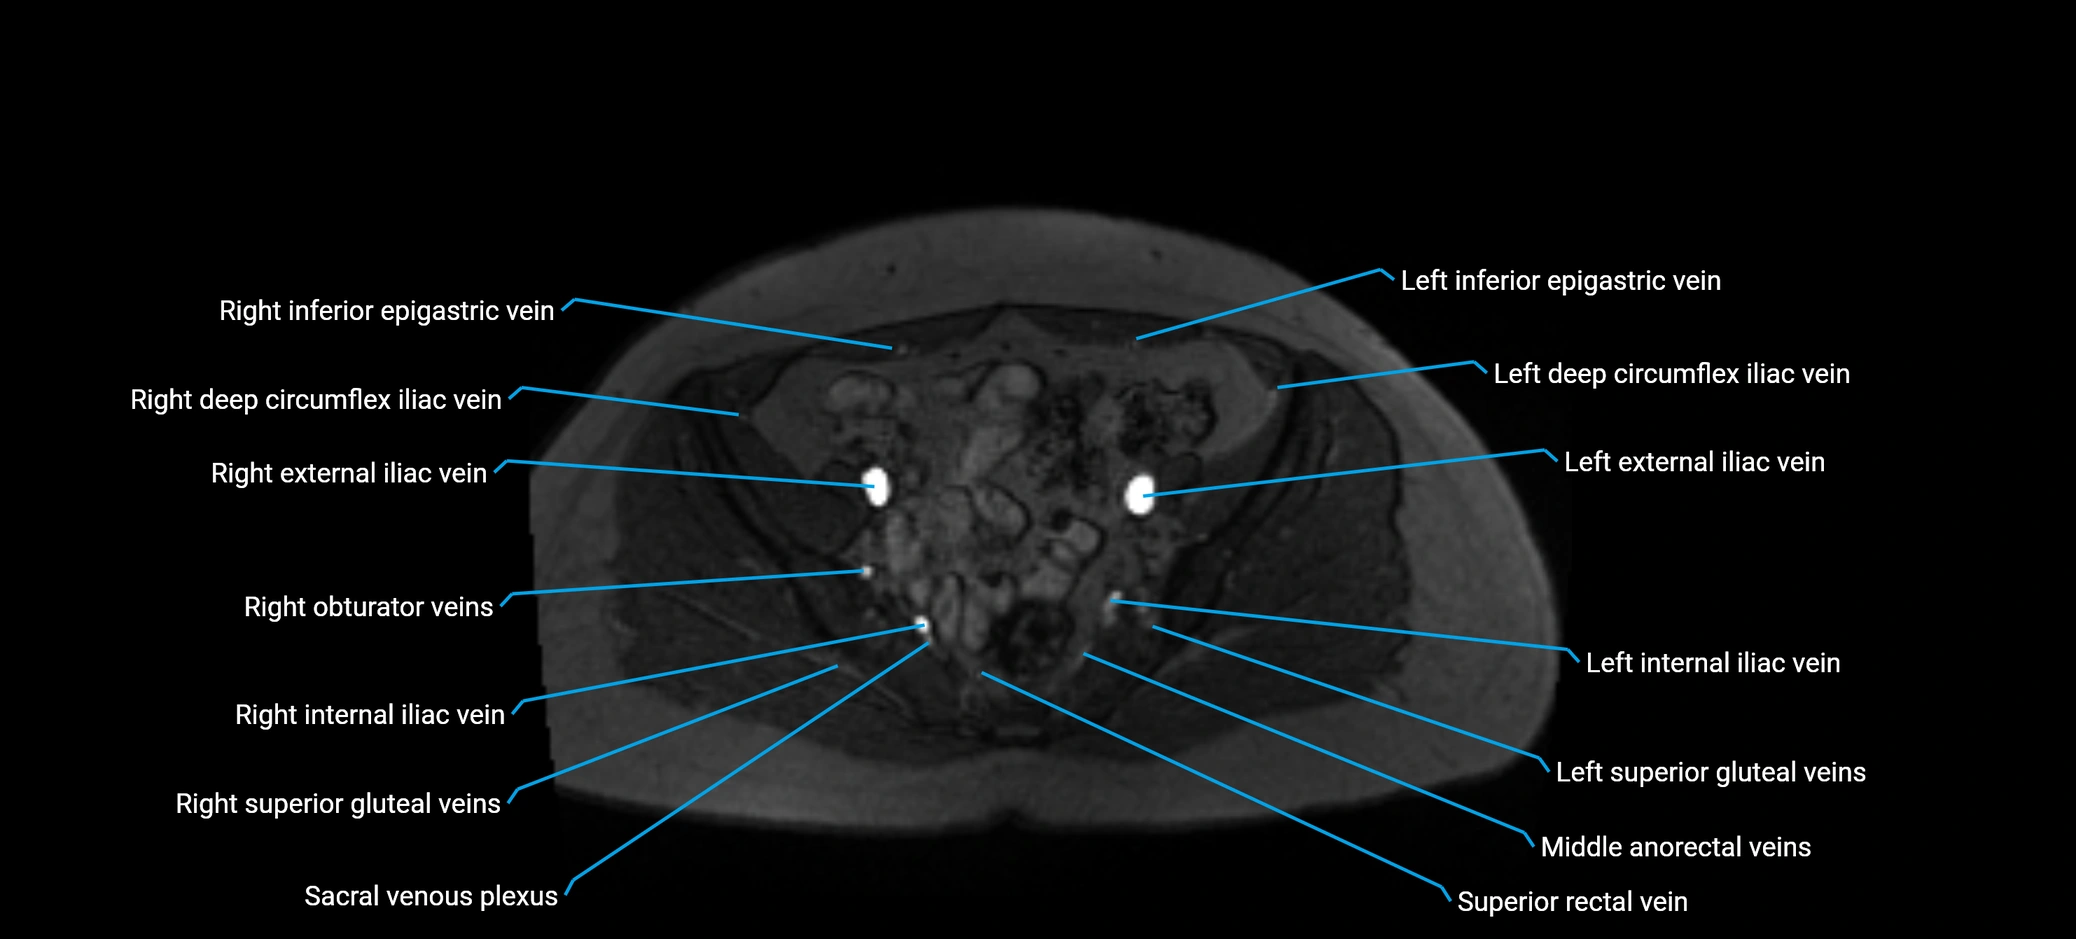

MRI image

image